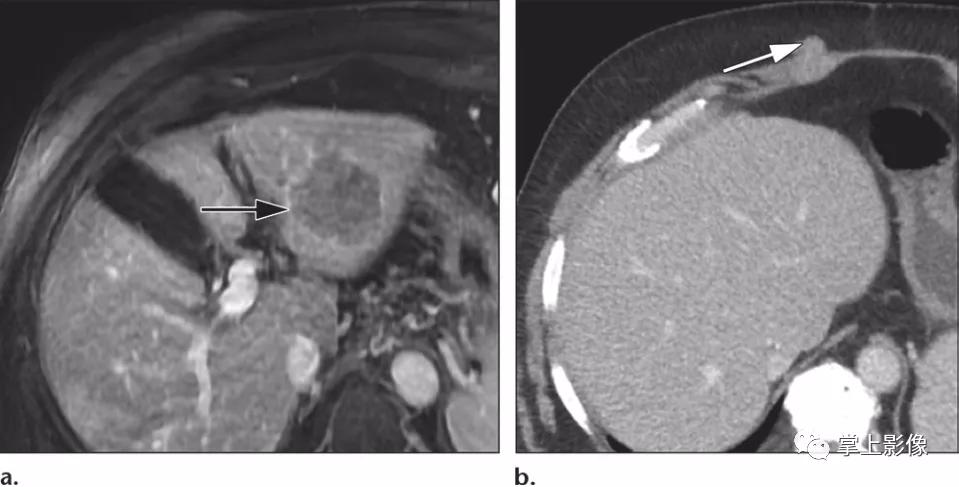

68岁男性肝硬化和肝细胞癌患者,先前活检轨迹的种植性转移性。(A)轴位增强T1加权MR图像显示左侧(箭头)边缘强化的肿块,为肝细胞癌病灶及其特征。患者接受了经皮穿刺活检,结果证实了影像诊断。(B)患者接受肝移植后获得的轴位增强CT图像显示先前经皮穿刺活检轨迹的种植性转移性(箭头)